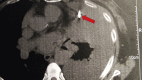

Re-biopsy after relapse of targeted therapy. T790M after epidermal growth factor mutation, where and why based on a case series

Guidelines for the treatment of non-small cell lung cancer adenocarcinoma positive in epidermal growth factor mutations indicate tyrosine kinase inhibitors. There are currently three tyrosine kinase inhibitors that can be used as first line treatment: gefitinib, erlotinib and afatinib. Regarding erlotinib and afatinib dosage can be modified in the case of severe adverse effects. In the case of disease relapse investigation for T790M mutation has to be made either with re-biopsy or liquid biopsy and osimertinib has to be administered when T790M is diagnosed. Based on a case series we indicate which is the best approach for T790M mutation.